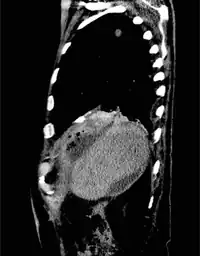

For bronchobilary fistula, the following tests are performed: 1) ultrasound abdomen, may show subdiaphragmatic collection around the surface of the right lobe of the liver. 2) preoperative chest X-ray, may demonstrate mild to moderate right-sided pleural effusion without an active lung pathology. 3) CT scan, may reveal focal collection along the liver's right lateral margin, which can be communicating with one of the right lower lobe bronchi, supporting the diagnosis of a BBF.[1]